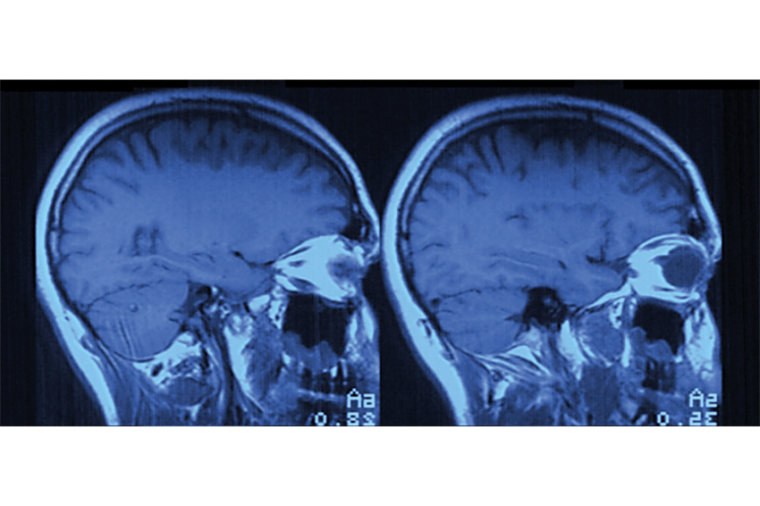

Egal ob Voruntersuchung, geplanter Eingriff oder Not-OP: mit bildgebenden Verfahren, beispielsweise durch einen Computertomografen (CT) erstellte 3D-Bilder, können sich Mediziner ein realistisches Bild vom Inneren des Patienten machen, um verletzte oder befallene Körperteile zu untersuchen und eine möglichst genaue Diagnose zu stellen. Sogar während des Eingriffs kommen solche Röntgensysteme zum Einsatz, um die behandelten Körperteile in Echtzeit darzustellen.

Digitale Bildverarbeitung ist dabei heute Standard, da auf diese Weise erstellte Röntgenbilder leichter interpretiert werden können als analog erstellte. Dennoch gibt es Schwachpunkte: So kann es durch Sensor- oder Spannungsquellen-bedingtes Rauschen zu einer Unschärfe beziehungsweise Kontrastminderung in der gesamten Aufnahme kommen – und damit zu Spielraum für Interpretationen in der Diagnose. So kann es vorkommen, dass die Materialdicke fehlerhaft angezeigt wird. Ziel ist es daher, dieses Bildrauschen im digitalen System so weit wie möglich zu reduzieren.